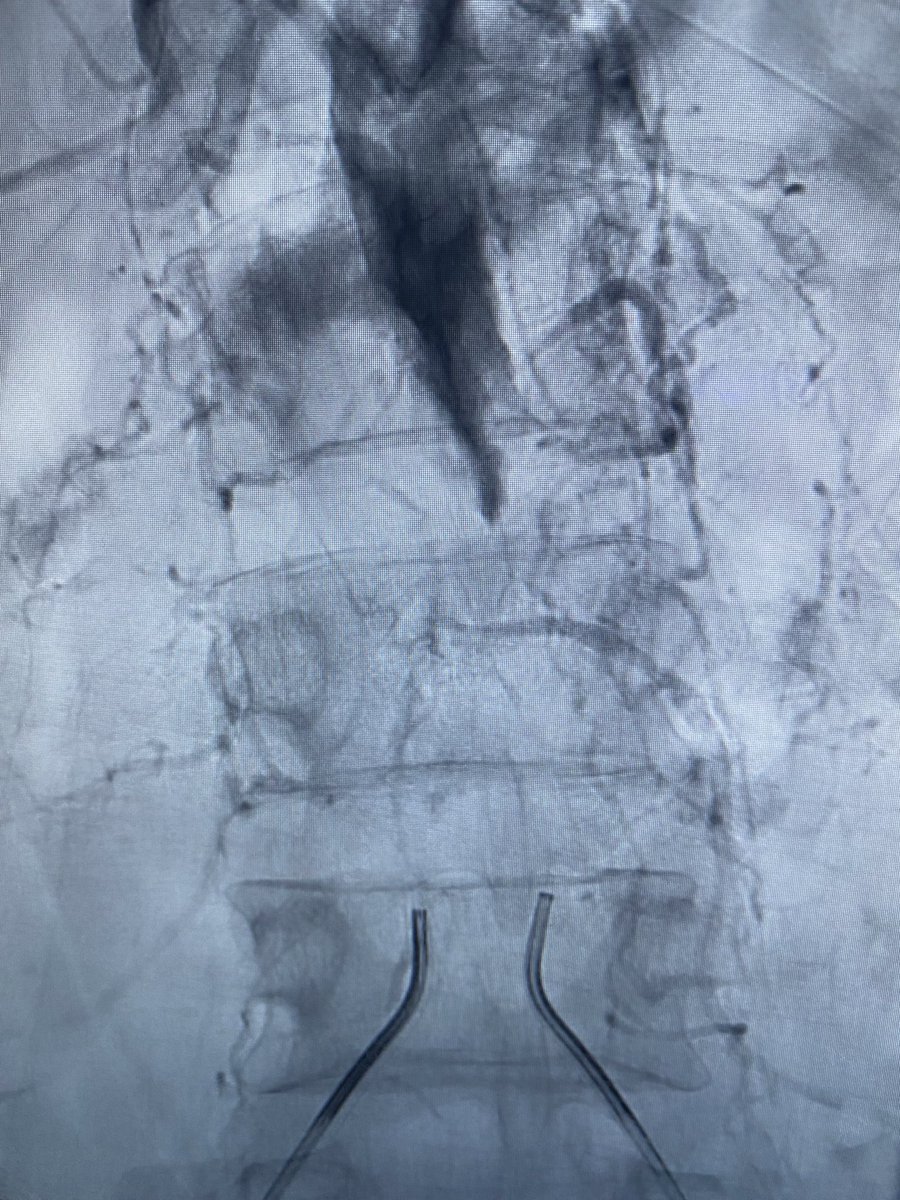

الحمدلله تم العبور الى شريان اليسار و من ثم العبور الى شريان اليمين اعادة التصوير ثم التوسيع ثم التخطيط لمنطقة الهبوط بالدعامة ثم اعادة بناءً الشريان الابهر و الحرشفي معا بفضل ربي.

كانت دقائق صمت و تفكير . بسم الله قبل التصوير النهائي دقات القلب تزداد كانت خوف ممزوج بفرح اي انفجار في الشريان يكلف الكثير .. بسم الله تصوير يا الله يا لجمال النتيجة 😍 الزملاء يتابعون بشوق من غرفة التحكم كانت متابعتهم كحماس متابعتنا لفريق المنتخب ضد الأرجنتين الجميع مهنئاً